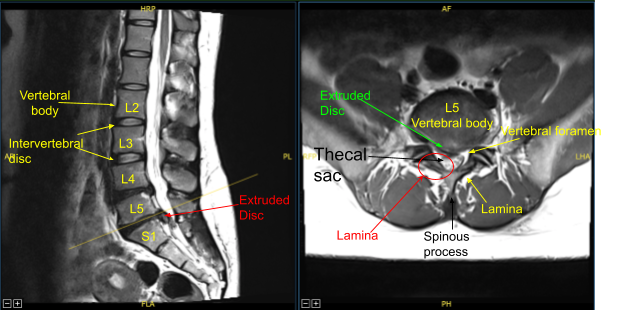

Case Study: Minimal Invasive (Tubular) Right L5 Laminotomy with L5-S1 Microdiscectomy and S1 Nerve root neurolysis

The patient presented with signs and symptoms of right lower extremity weakness with a very large herniated intervertebral disc at L5-S1 on the MRI causing severe compression of the thecal sac and S1 nerve root on the right side. Due to neurological deficit and severe pain, surgery was recommended to decompress the lumbar spine.

An electric high-speed drill with sterile irrigation was used to perform right L5 laminotomy exposing the ligamentum flavum which was detached rostrally from the ventral lamina with an angled curette and reflected caudally and then resected in a piecemeal fashion with 2 and 3 mm Kerrison rongeurs exposing the intact dura.

The Right S1 nerve root appeared splayed under pressure and inflamed. There was a herniated disc apparent in the axilla between the thecal sac and the right S1 nerve root.